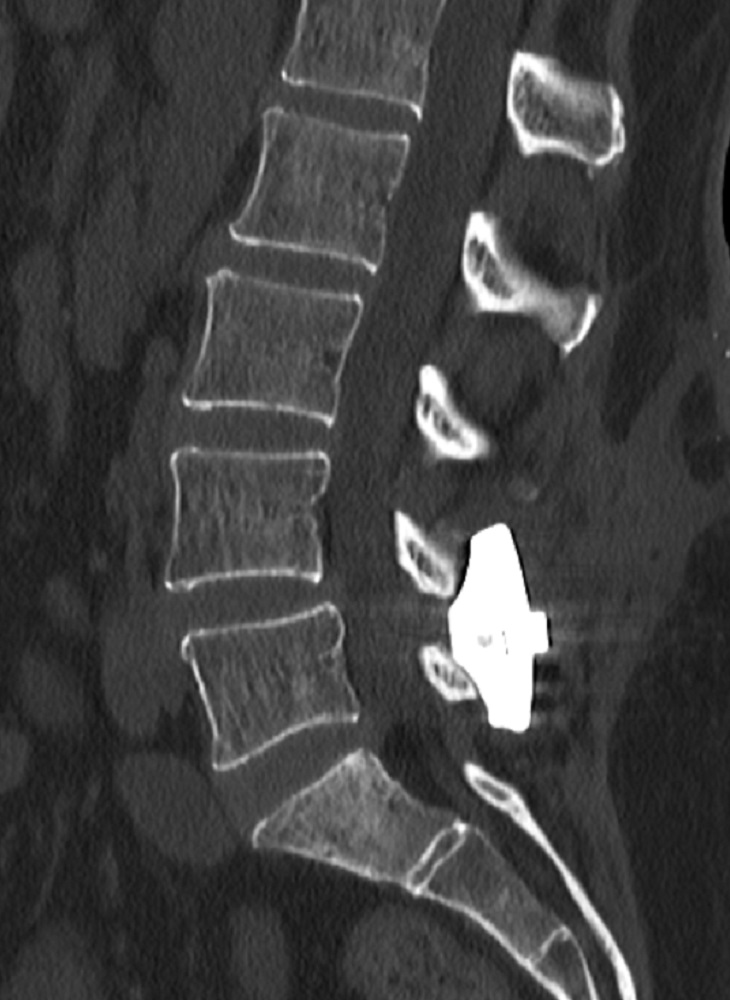

INSPAN, LLC is privately owned by the KICVentures Group and is focused on advancing the platform of patented interspinous fixation technology. The Inspan device has a proven ten-year track record with thousands implanted since FDA clearance in 2010. https://myinspan.com/

Inspan Sawbone Demonstration by Prof. Dr. Kingsley R. Chin